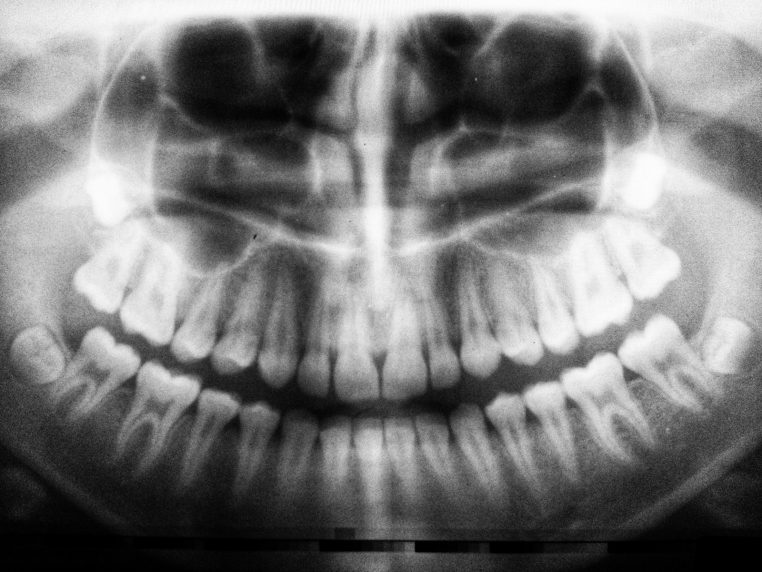

« L’orthodontiste est entré dans la salle et a affiché les radios sur l’écran », raconte la maman à Newsweek. « Nous les avons vues en même temps et pendant plusieurs minutes, nous avons essayé de comprendre ce que nous étions en train d’observer. »

Sur l’image, un petit objet métallique apparaissait, coincé dans les sinus de la fillette. La mère était stupéfaite et n’avait aucune idée de ce que cela pouvait être. Mais une personne dans la pièce savait exactement ce qu’il s’était passé : sa fille.